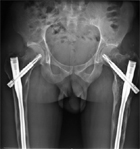

Mr D. 28 ans présente une dysplasie fibreuse de plusieurs sites osseux. Il a été opéré de nombreuses fois pour les sites fémoraux.

Les radiographies à basse énergie de type EOS® permettent de suivre l’évolution structurale avec une irradiation 10 fois inférieure à celle d’une radiographie standard.

On note une atteinte...